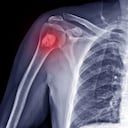

Cuando no se cuidan, es posible que se desarrolle osteoporosis, un padecimiento que se caracteriza por una disminución de la densidad de los mismos como consecuencia de la pérdida del tejido óseo normal. Esto genera una baja de la resistencia frente a traumatismos, con la consiguiente aparición de fracturas.

La Biblioteca Nacional de Medicina de Estados Unidos indica que el calcio es clave para mantener densos los huesos, por lo que es esencial su consumo. La densidad ósea baja puede provocar que los huesos se vuelvan quebradizos y frágiles.